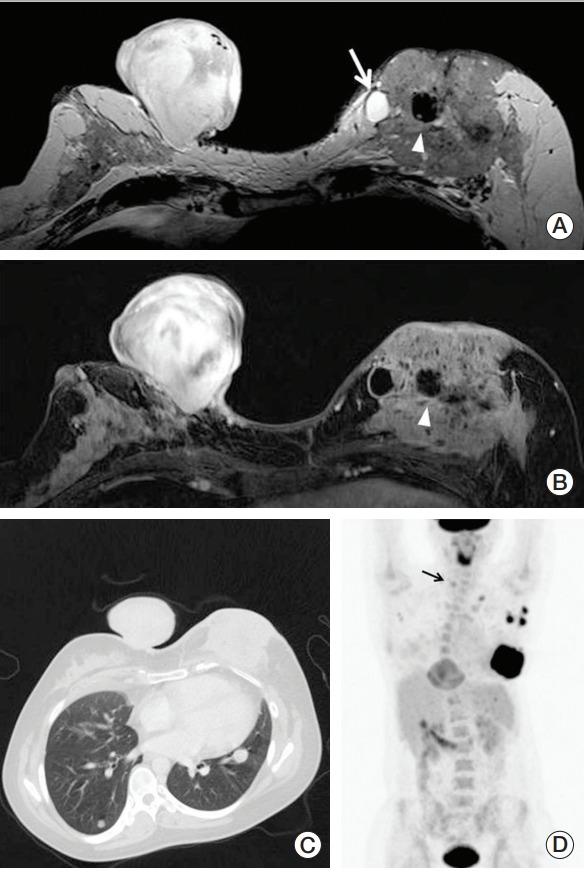

PTEN hamartoma tumor syndrome is a spectrum of disorders characterized by unique phenotypic features including multiple hamartomas caused by mutations of the tumor suppressor gene PTEN. Cowden syndrome and Bannayan-Riley-Ruvalcaba syndrome are representative diseases, and both have several common clinical features and differences. Because PTEN mutations are associated with an increased risk of malignancy including breast, thyroid, endometrial, and renal cancers, cancer surveillance is an important element of disease management. We report a germline mutation of the PTEN (c.723dupT, exon 7) identified in a young woman with a simultaneous occurrence of breast cancer, dermatofibrosarcoma protuberans, and follicular neoplasm. This case suggests that it is critical for clinicians to recognize the phenotypic features associated with these syndromes to accurately diagnose them and provide preventive care.

PTEN 错构瘤肿瘤综合征是一种由肿瘤抑制基因 PTEN 突变引起的多种错构瘤为特征的疾病谱。考登综合征和班纳扬-赖利-鲁瓦尔卡巴综合征是其代表性疾病,两者均具有一些共同的临床特征和差异。由于 PTEN 突变与包括乳腺癌、甲状腺癌、子宫内膜癌和肾癌在内的恶性肿瘤风险增加相关,因此癌症监测是疾病管理的重要内容。我们报告了一名年轻女性同时发生乳腺癌、隆突性皮肤纤维肉瘤和滤泡性肿瘤,发现其存在 PTEN(c.723dupT,外显子 7)种系突变。该病例提示临床医生识别与这些综合征相关的表型特征对于准确诊断并提供预防保健至关重要。